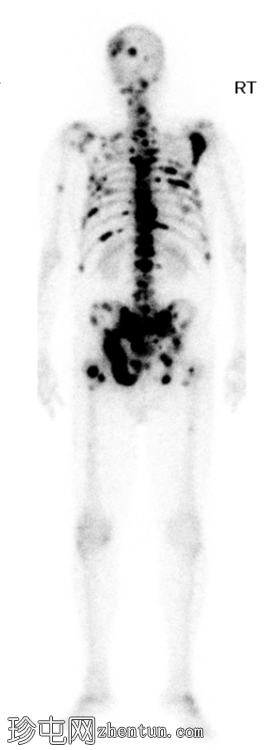

Tc99m MDP骨扫描

全身

前位

脊柱、肋骨、骨盆、颅骨、肩胛骨、胸骨、左侧肱骨和双侧股骨干可见多处放射性示踪剂摄取异常增高,与SPECT-CT扫描图像上显示的硬化病灶相对应。双肾未见放射性示踪剂活性。

骨骼内多处局灶性放射性示踪剂摄取增高,符合骨转移;肾脏内无放射性示踪剂活性,与超扫描结果一致。